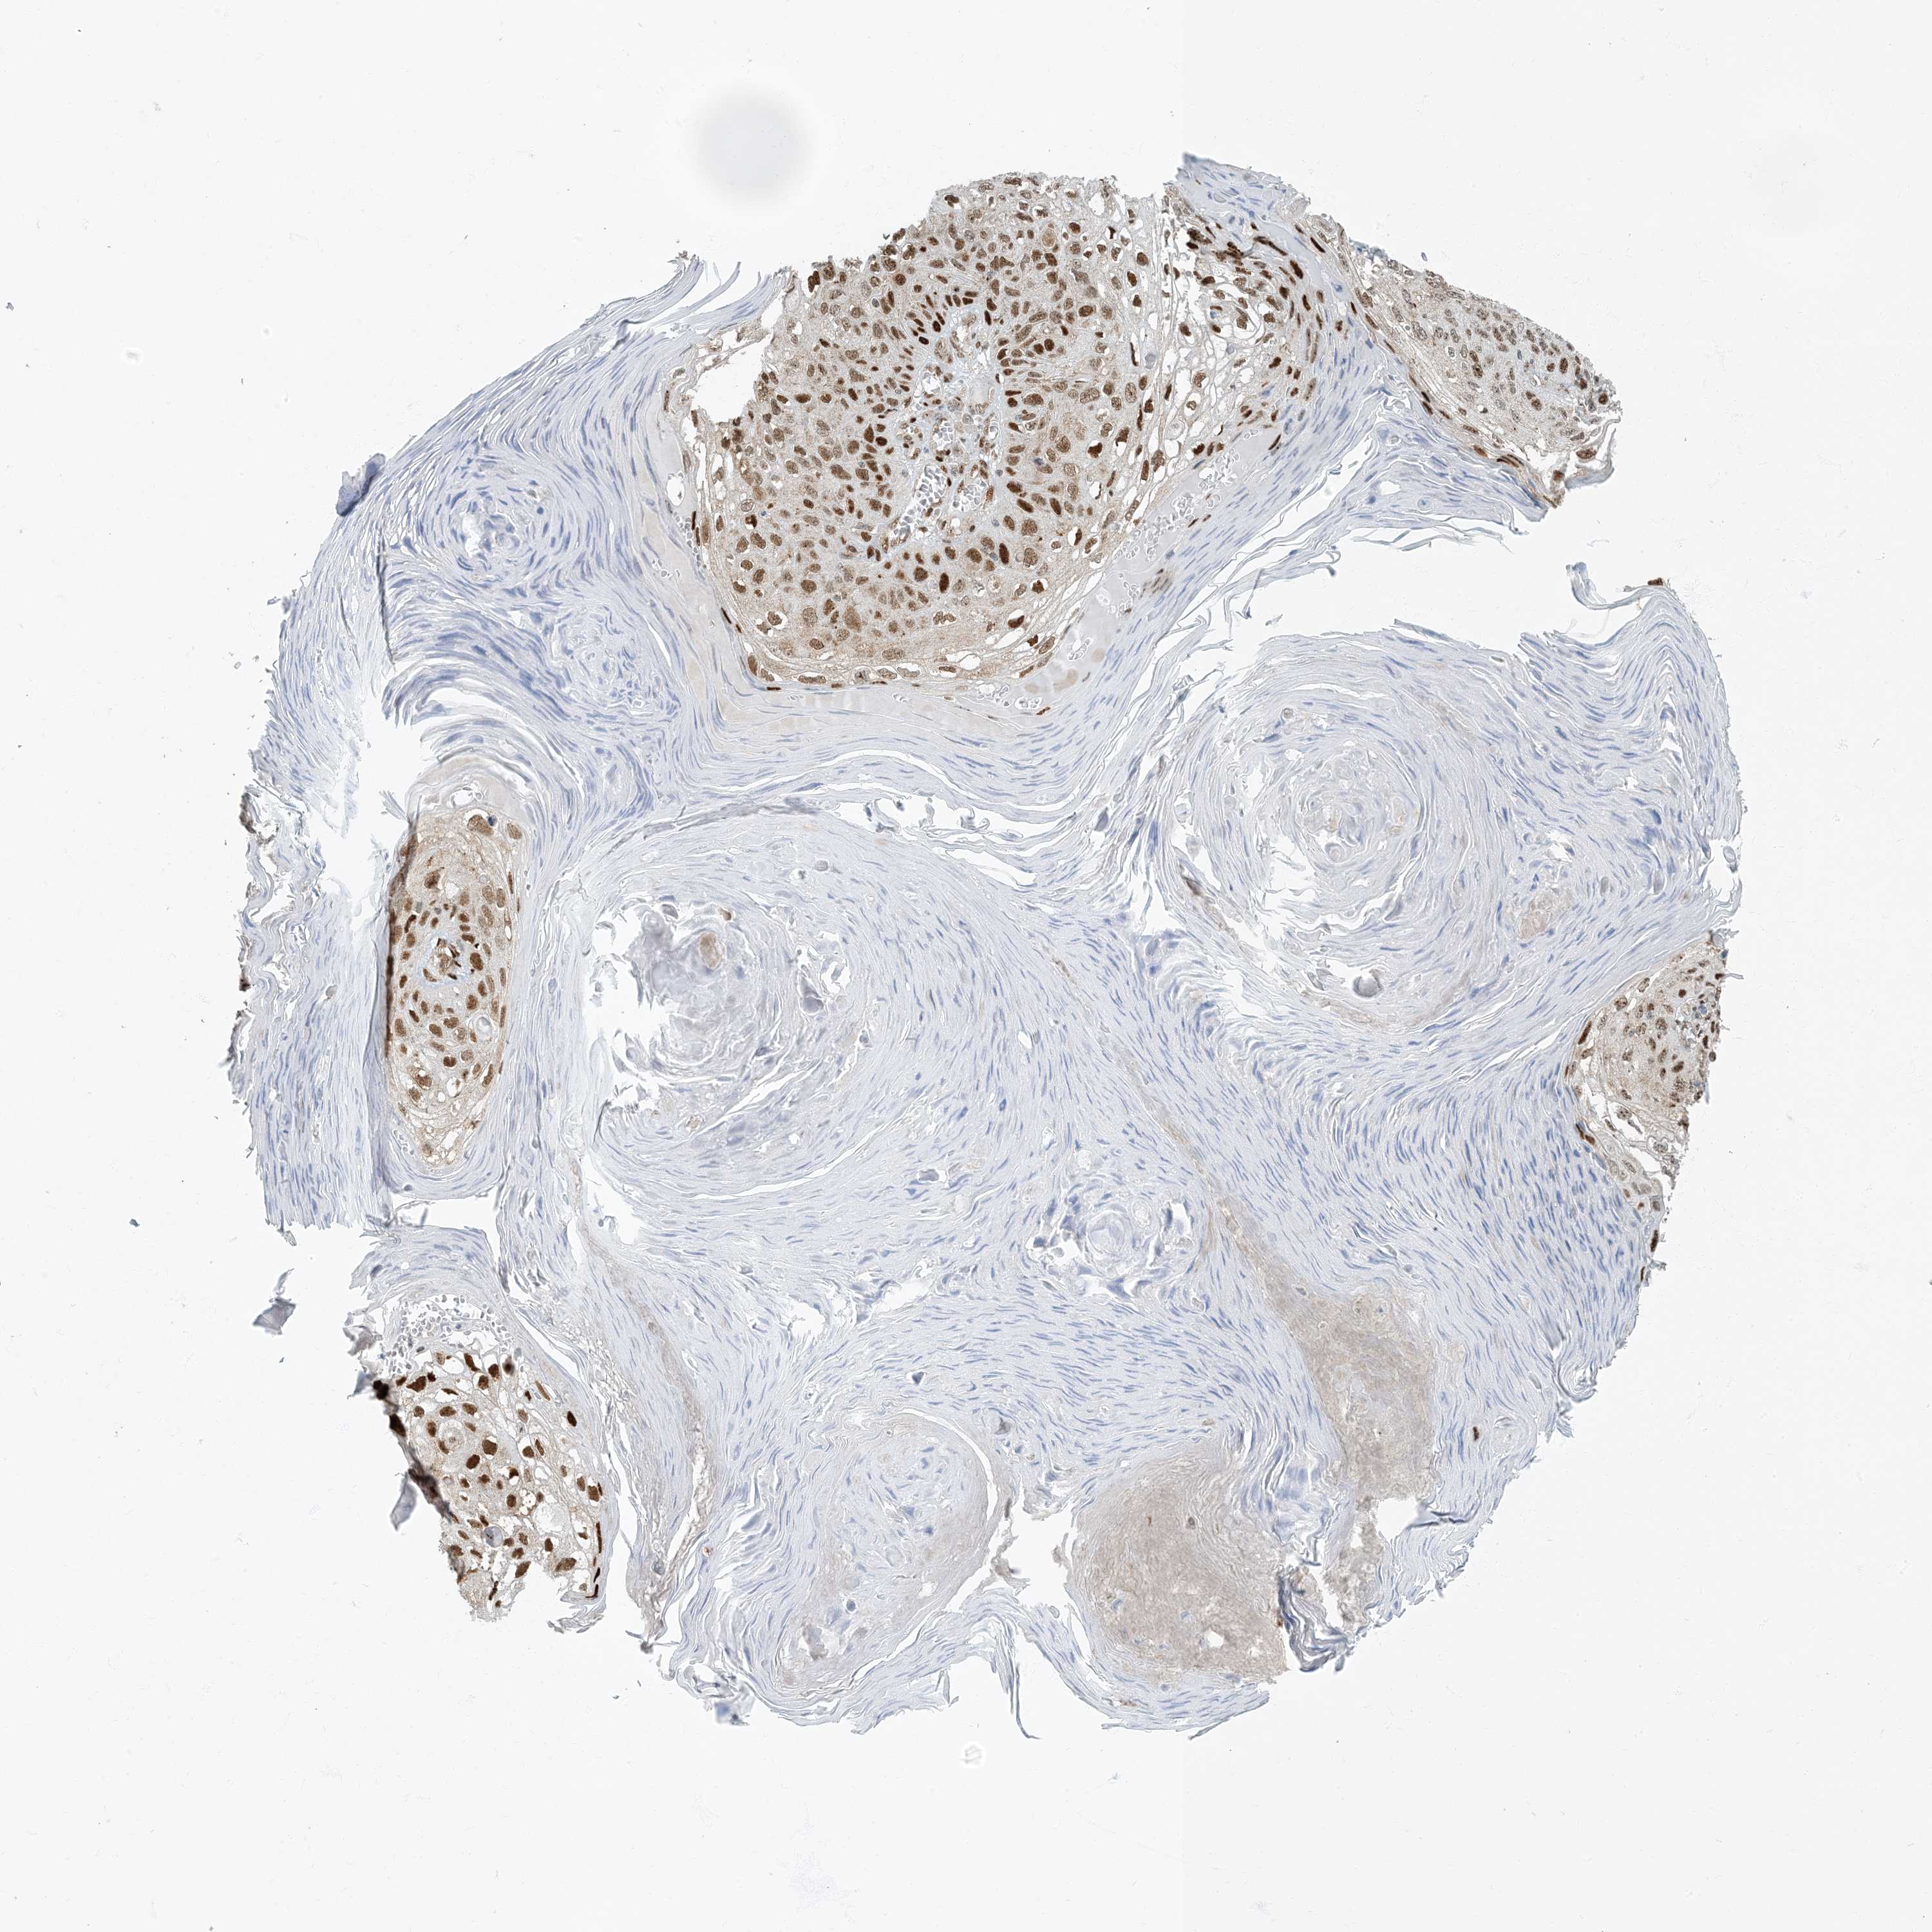

SKIN CANCER - Protein expressioni

A mouse-over function shows sample information and annotation data. Click on an image to view it in a full screen mode. Samples can be filtered based on level of antibody staining by selecting one or several of the following categories: high, medium, low and not detected. The assay and annotation is described here.

Each image is clickable and will lead to virtual microscopy that enables deeper exploration of all samples and also displays staining intensity scores, fraction scores and subcellular localization as well as patient and tissue information for each sample.

Antibody CAB009017

Staining

High

Intensity

Strong

Quantity

>75%

Location

Nuclear

Squamous cell carcinoma in situ, NOS